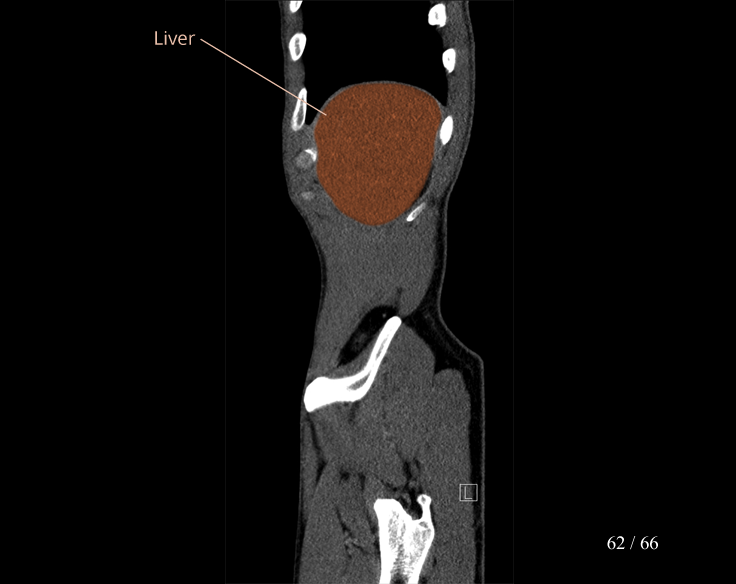

Body

Covers abdominal CT anatomy.